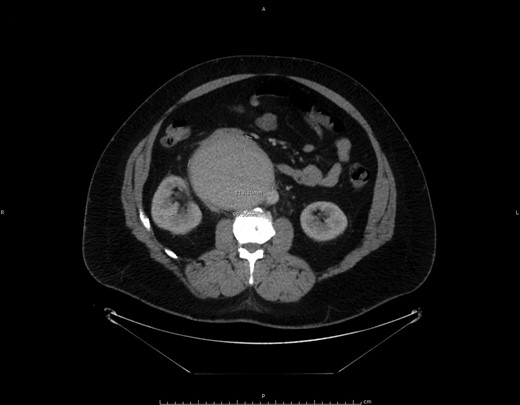

A 42-year-old patient with a history of clinical Stage I testicular non-seminomatous germ cell tumor (NSGCT) status post-left radical orchiectomy in 1986 (the exact pathology from his orchiectomy was not available) without additional treatment presented with right testis, back and flank pain. An abdominal computed tomography (CT) scan showed a retroperitoneal mass measuring 11.3 × 9.3 × 4.6 cm in the precaval area (Fig. 1) with negative tumor markers including β-HCG and alpha-fetoprotein. The patient underwent a testicular ultrasound of the right testis that showed microlithiasis but no hypodense mass. An exploratory laparoscopy with biopsy showed morphological features suggesting retroperitoneal idiopathic fibrosis. However, the clinical and imaging features as assessed by the urologist and oncologist were felt to be inconsistent with this possibility. The patient, therefore, underwent a CT-guided fine needle aspiration of the mass that showed extensively necrotic tumor.